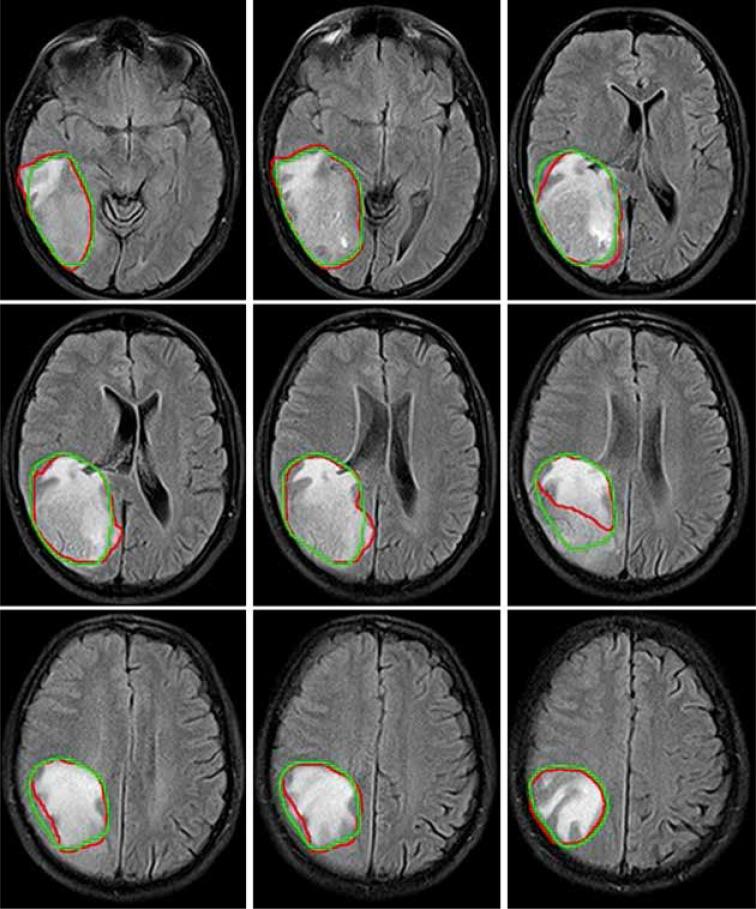

In this study, the modified Segmentation-Net (SegNet) model with deep supervision and residual-based skip connection mechanism was trained on 259 glioblastoma patients from the Multimodal Brain Tumour Image Segmentation Benchmark (BraTS) 2019 Challenge dataset for segmentation of gross tumour volume (GTV). Then, the pre-trained CNN model was fine-tuned with an independent clinical dataset ( = 37) to perform the CTV segmentation. In the process of fine-tuning, to generate a CT segmentation mask, both CT and MRI scans were simultaneously used as input data. The performance of the CNN model in terms of segmentation accuracy was evaluated on an independent clinical test dataset ( = 15) using the Dice Similarity Coefficient (DSC) and Hausdorff distance. The impact of auto-segmented CTV definition on dosimetry was also analysed.

The proposed model achieved the segmentation results with a DSC of 89.60 ± 3.56% and Hausdorff distance of 1.49 ± 0.65 mm. A statistically significant difference was found for the Dmin and Dmax of the CTV between manually and automatically planned doses.

在本研究中,具有深度监督和基于残差的跳跃连接机制的改进型分割网络(SegNet)模型在来自多模态脑肿瘤图像分割基准(BraTS)2019挑战赛数据集的259例胶质母细胞瘤患者上进行训练,以分割肿瘤总体积(GTV)。然后,使用一个独立的临床数据集(n = 37)对预训练的CNN模型进行微调,以执行CTV分割。在微调过程中,为了生成CT分割掩码,CT和MRI扫描同时用作输入数据。使用骰子相似系数(DSC)和豪斯多夫距离,在一个独立的临床测试数据集(n = 15)上评估CNN模型在分割准确性方面的性能。还分析了自动分割的CTV定义对剂量测定的影响。

所提出的模型实现了分割结果,DSC为89.60 ± 3.56%,豪斯多夫距离为1.49 ± 0.65 mm。在手动计划剂量和自动计划剂量之间,CTV的Dmin和Dmax存在统计学显著差异。